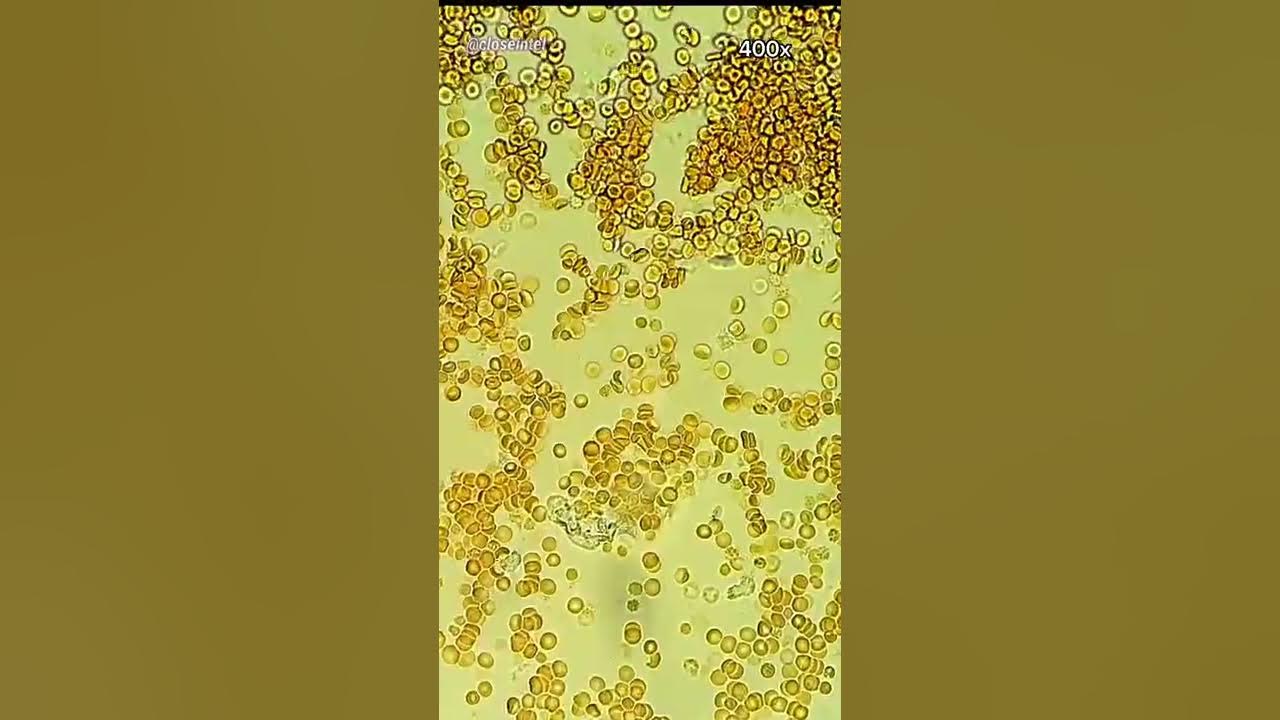

Drop Of Blood Under Microscope . Carefully place a coverslip over the drop of blood. Add a drop of stain to the blood to make the cells easier to see. Up close, the smear shows how many of each type of blood cell are present. A blood smear is a test that allows a healthcare provider to take a close look at a blood sample under a microscope. A blood smear is a drop of blood spread thinly onto a glass slide that is then treated with a special stain and examined under. That’s because the cell is still in its developmental stage. We will look into the blood cells under the microscope to learn unique techniques and processes for a fun and exciting experiment. The sizes, shapes, and colors of the cells can be seen, along with any parasites or fragments in the blood. When you look at a blood smear, it's best to have a plan, and it's best to try to follow it each time. Place a drop of blood onto a microscope slide. If you can carry out both in the same session, it is easier to manage dealing with contaminated.